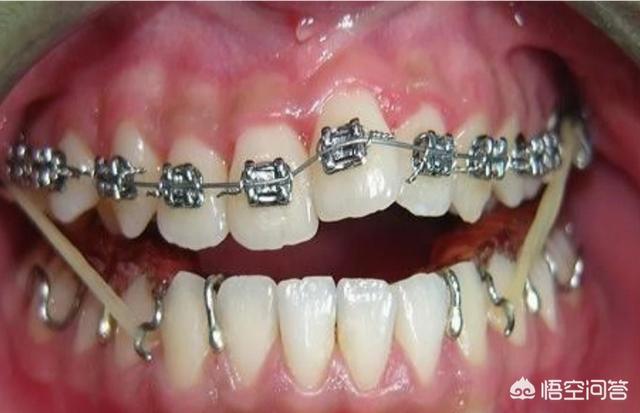

关于正畸不管你用传统方法还是最新的隐形矫正,想要达到矫正目的首先是要获取间隙(牙齿本身稀疏除外)。

而获取间隙的方法无外乎是减数(拔牙)、减径(片切牙缝)、扩弓(扩展狭窄的牙弓)此外还有推磨牙向后。

临床常有不拔牙正畸的病例,结果把一类畸形矫治成另一类畸形。

(图片来源于网络)